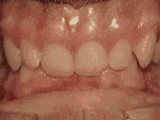

案例二

小王(16岁)兔牙,门牙外凸

门牙龅牙,每次露齿笑的时候内心好忐忑,好怕别个用那种眼神看我,但是不想戴牙套....你懂得的!

看,这是我的牙套,隐形的哦~妈妈听说隐形牙套效果很好,就为我报名了。隐形牙套真的,超赞的,同学都不知道我戴了牙套,哈哈~

嘻嘻,看,龅牙不见了,以后可以大大方方的露齿笑了~